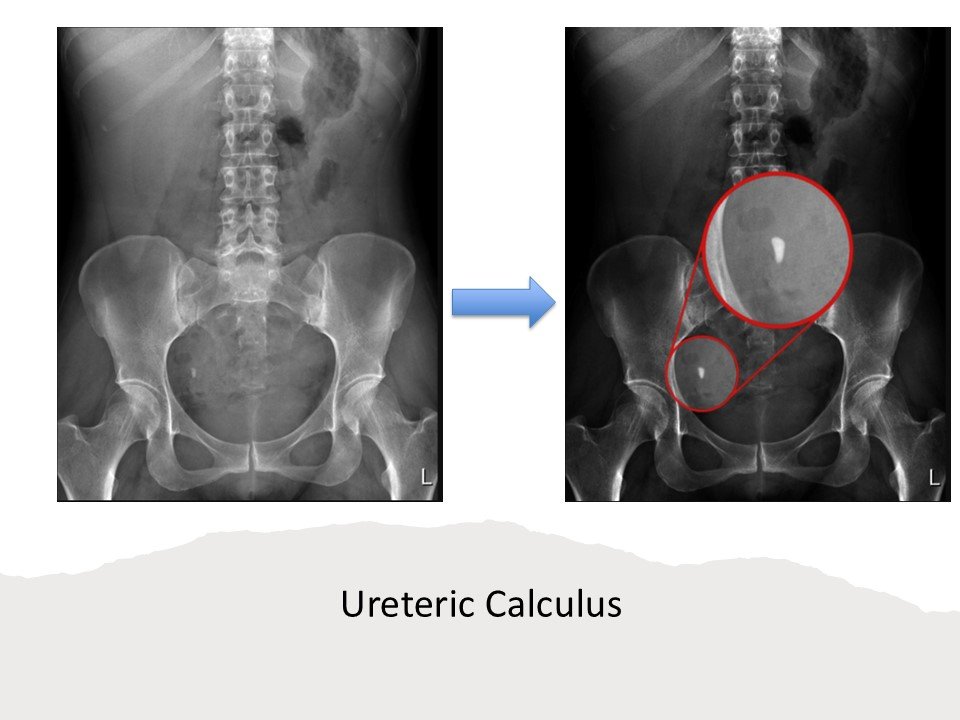

Ureteric Calculus:

1)Hyperdense focus along ureteric course.

2)Soft-tissue rim sign favors stone over phlebolith.

3) Associated with Upstream hydroureter & hydronephrosis.

- Radiopaque stones appear as dense white opacities.

- Visibility depends on stone composition and size.

Stones Seen:

- Calcium oxalate, phosphate, struvite.

a) Plain X-ray KUB showing a large radio-opaque density in the region of Right upper ureter, b) IVU shows presence of right upper ureteric calculus with prompt uptake and excretion of contrast from both renal units.